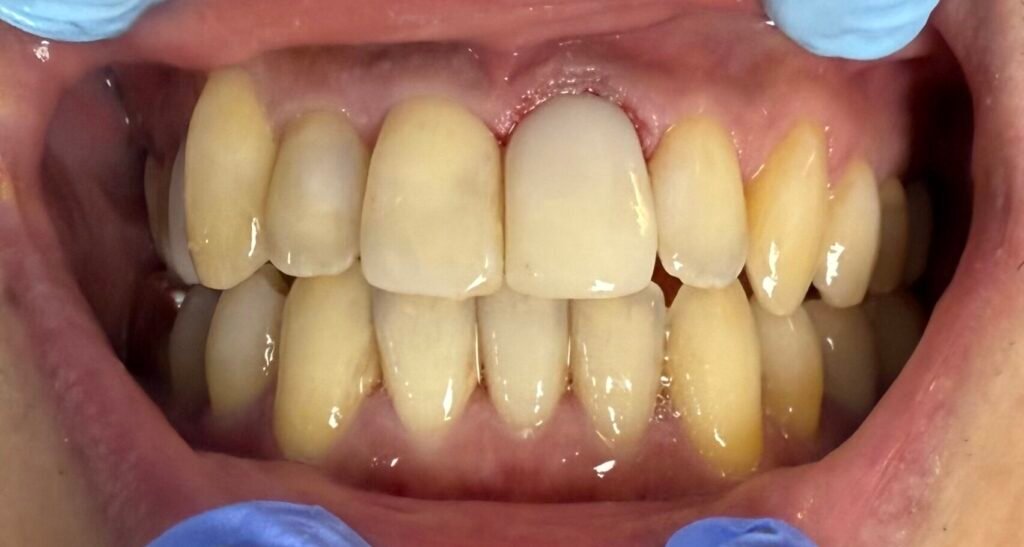

Scaling & Root Planing (Deep Cleaning)

Our specialists remove plaque and calculus from above and below the gum line, smoothing the roots to encourage the gum tissue to reattach to the teeth.

Maintenance & Support

Successful treatment requires ongoing care. We provide personalized home care strategies and regular professional cleanings to ensure the infection does not return.